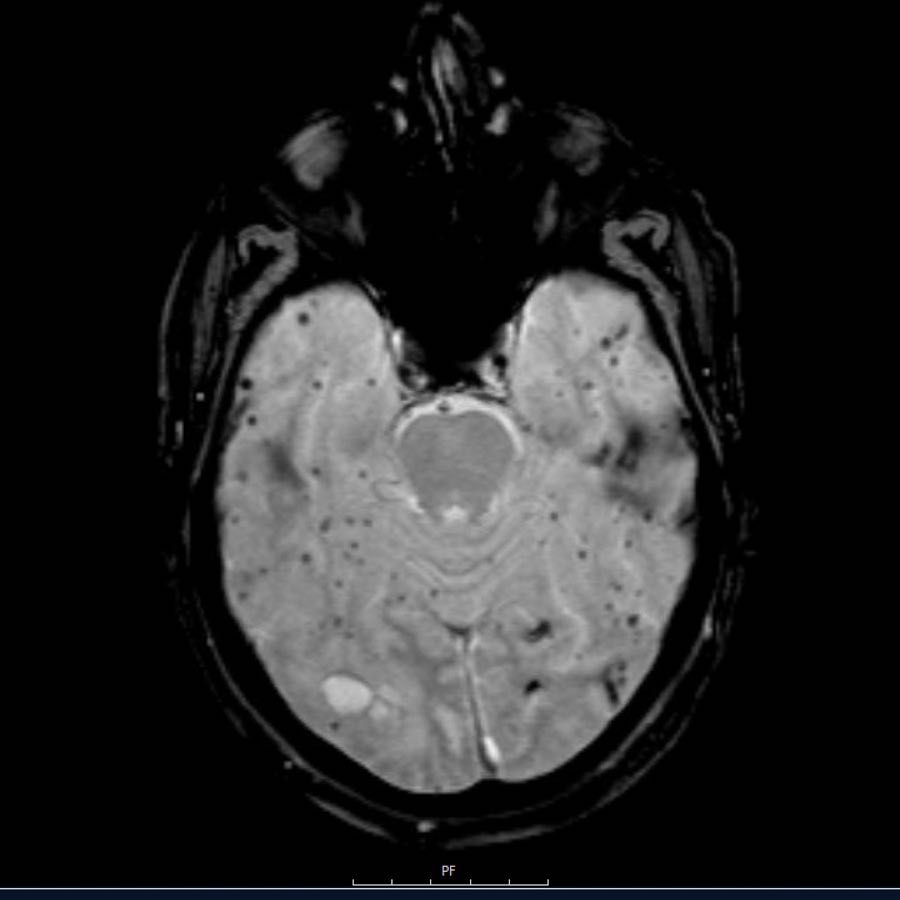

Các ổ xuất huyết nhỏ này còn được gọi là xuất huyết vi thể (microbleeds).

Lưu ý số lượng rất nhiều các ổ xuất huyết nhỏ này, phân bố chủ yếu ở vùng ngoại vi của não.

Bệnh nhân này nhập viện với hình ảnh khối máu tụ tiểu não.

Tiếp tục xem hình ảnh chuỗi xung T1W…

Chuỗi xung T1W cho thấy ổ xuất huyết tăng tín hiệu (mũi tên).

Xuất huyết nội sọ do tăng huyết áp cùng với CAA chiếm 80% nguyên nhân gây khối máu tụ trong nhu mô não.

Cần nghĩ đến CAA khi phát hiện nhiều ổ xuất huyết ngoại vi hoặc xuất huyết thùy ở bệnh nhân cao tuổi.